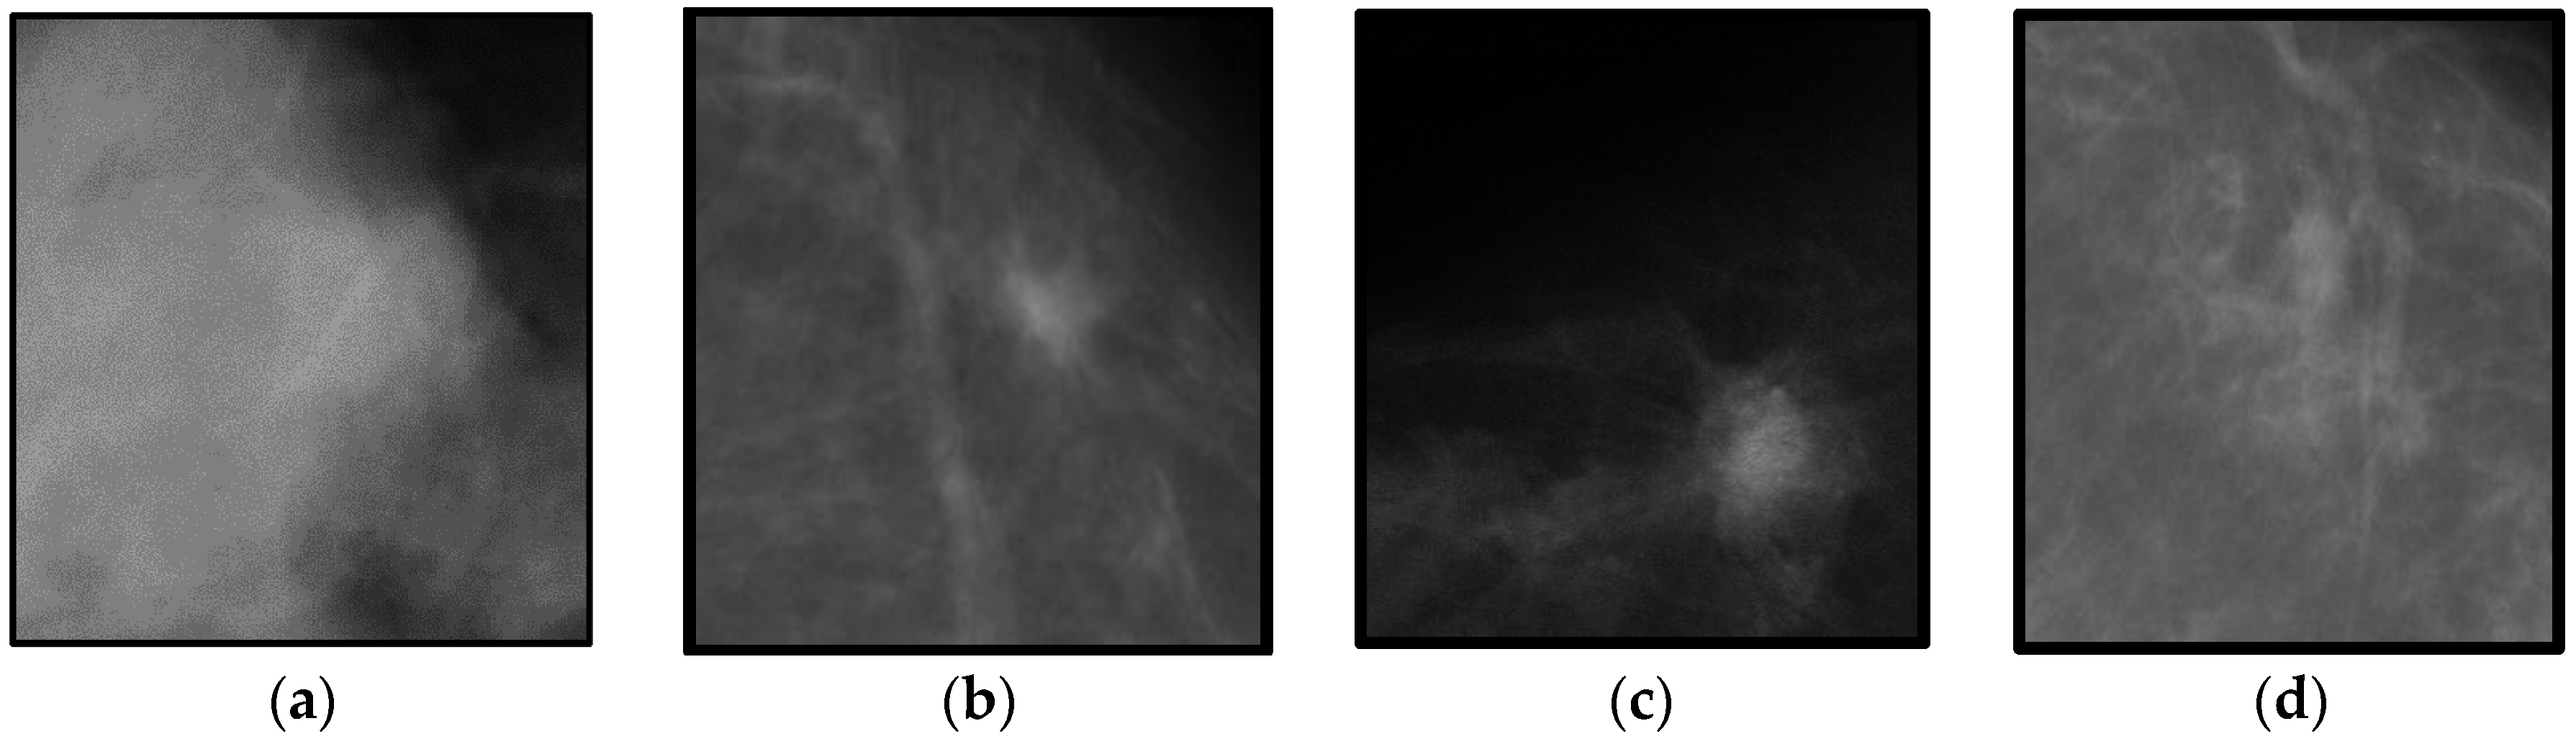

On the other hand, the classification accuracy of the proposed DeepCAD system with the sate-of-the-art classification algorithms such as CNN-Max-CAD-Qiu and CNN-CAD-Jiao by 10-fold cross validation test on the different dataset. This different features dataset is obtained from using masses that are not centered to the region-of-interest (ROI) image. An example of this dataset with un-centered masses are shown in

Figure 5. The significance accuracy is obtained by using DeepCAD system when compared to two other CNN-Max-CAD-Qiu and CNN-CAD-Jiao classification systems. The CNN-Max-CAD-Qiu system is overall better than CNN-CAD-Jiao but less effective than proposed DeepCAD system. The DeepCAD algorithm is performed well due to the fact that it selected most discrimination features, which is getting characteristics to maximize the deep margins. In future studies, the linear structures such as speculated lines and microcalcification features will also be extracted to enhance the classification accuracy.